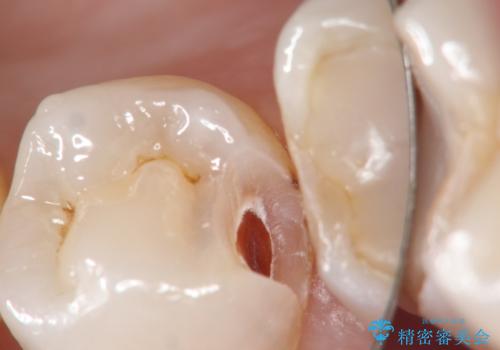

- 定期検診において虫歯を見つけた患者様です。

セラミックインレーにて修復治療をしています。

当院のセラミックインレーはすべてプレスという製法で製作しております。削り出しのものより精度が高く製作可能です。